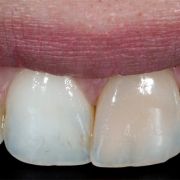

The tooth is discolored due to previous improper RCT. The discoloration is due to remnants of gutta percha and sealer inside the pulp chamber. The case was done by Dr Khalid Merdad and I.

Deep chroma is apparent in tooth #21 due to previous improper RCT.

to show the deep chroma from inside the tooth